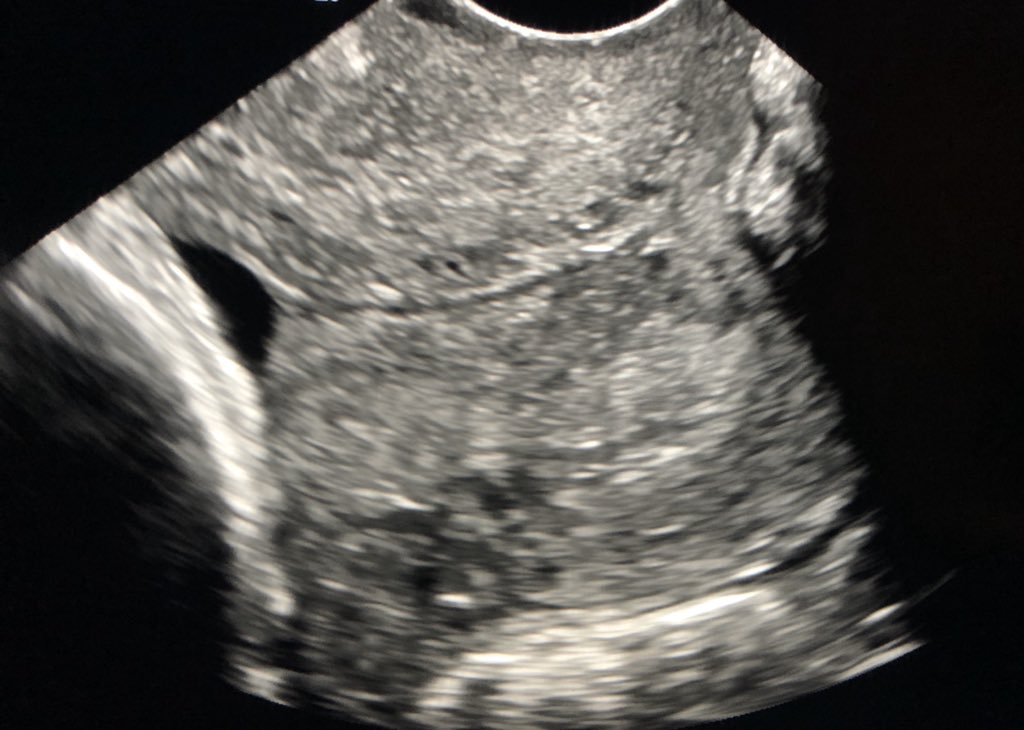

You can almost FEEL the retractile clot jiggling in this hemorrhagic ovarian cyst.pic.twitter.com/dCppOamvHu